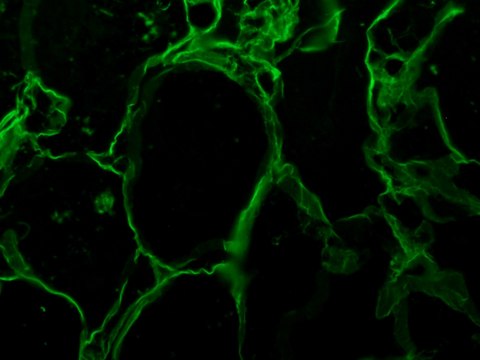

immunohistochemistry (formalin-fixed, paraffin-embedded sections): suitable, immunohistochemistry (frozen sections): suitable, indirect immunofluorescence: 1:20 using formalin-fixed, paraffin-embedded sections of human tissue, western blot: 1:50 using HS-68 human foreskin cell extract

Anti-Vimentin antibody produced in goat has been used in Immunohistochemistry and Western blot analysis.

The antibody localizes vimentin in normal and pathological tissue of mesenchymal derivation. The antibody shows wide cross-reactivity among mammalian species.